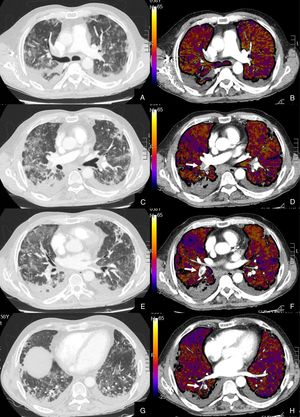

Paciente con COVID-19 con disnea, dolor torácico tipo pleurítico y elevación del D-dímero.

Imágenes axiales de una angiografía pulmonar con TC y mapa de yodo, con ventana de parénquima (A, C, E, G) desde lóbulos superiores hasta lóbulos inferiores y sus correspondientes imágenes del mapa de yodo (B, D, F, H).

Parénquima con extensa afectación en vidrio deslustrado y derrame pleural bilateral de pequeña cuantía. TEP unilateral en arteria lobar inferior derecha y segmentarias inferiores derechas (flechas). El mapa de yodo pone de manifiesto numerosas áreas de hipoperfusión (azules) parcheadas bilaterales (fundamentalmente en las zonas de pulmón afectado) por probable microtrombosis /alteraciones de la circulación en el lecho capilar.